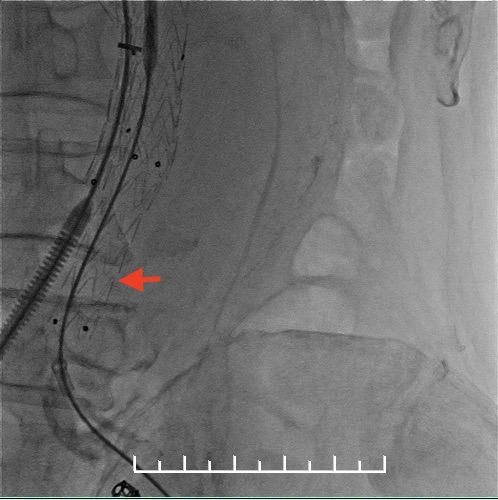

栓塞左侧髂内动脉。箭头处可见髂总动脉钙化扭曲明显,进出导管十分困难。

左侧放置第一枚髂腿支架(16mm*140mm,美敦力)

左侧放置第二枚髂腿支架(16mm*140mm,美敦力)